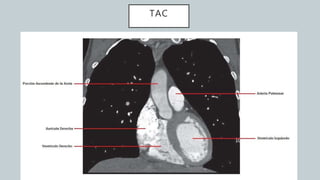

El documento detalla la anatomía del corazón y su ubicación en la caja torácica, incluyendo estructuras como las aurículas, ventrículos y arterias. También se abordan técnicas de diagnóstico por imagen, como radiografías y TAC, para visualizar la morfología cardíaca. La información está dirigida a estudiantes de medicina y profesionales interesados en la anatomía cardíaca.